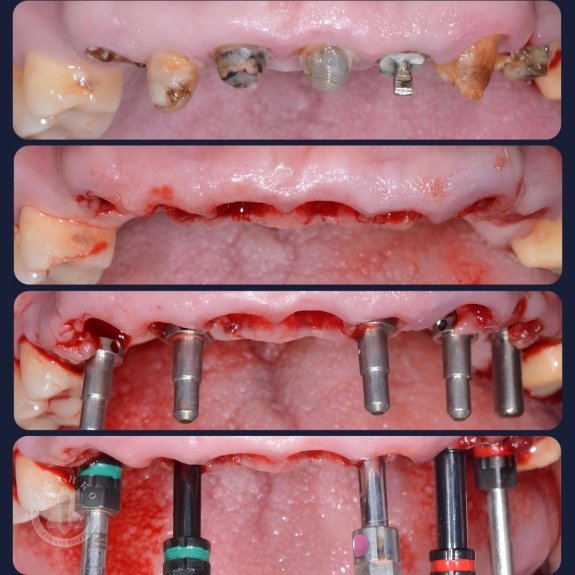

🦷 После снятия старых коронок и оценки состояния опорных зубов под ними, стало понятно, что они не подлежат восстановлению. Это происходит, в том числе, из-за удаления нервов в этих зубах. В результате человек не чувствует, когда зубы портятся, и не принимает своевременных мер. В целом, тема объемная и сложная, и ее трудно осветить тезисно в рамках одного поста. Если вкратце, профилактика и посещения доктора раз в 6 месяцев, даже если ничего не беспокоит, – залог здоровья. Вернемся к теме ➡️

📋Была спланирована и проведена операция по удалению непригодных для дальнейшего лечения зубов и установке высокопрочных титановых имплантов на место удаленных зубов.